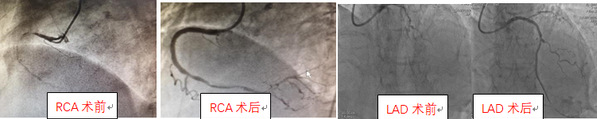

造影顯示患者的心臟中樞道路——原先重度狹窄扭曲鈣化的前降支次全閉塞了。手術(shù)參加人員楊煜主任、陸遠(yuǎn)主任、張敏、段洋主治醫(yī)師按照術(shù)前制定的手術(shù)策略:首先IABP支持下,導(dǎo)絲順利通過、球囊小壓力擴(kuò)張后恢復(fù)前降支的血流、遠(yuǎn)端引流良好;第二步高速旋轉(zhuǎn)(15萬轉(zhuǎn)/分)旋磨頭,5次短促旋磨一點(diǎn)點(diǎn)通過鈣化病變,老人心率血壓均穩(wěn)定,臺上醫(yī)生們懸著的心終于放下了;第三步高壓球囊擴(kuò)張后,IVUS(血管內(nèi)超聲)指引下支架順利植入,手術(shù)成功(圖四)。

圖四:術(shù)前術(shù)后冠狀動脈血管對比